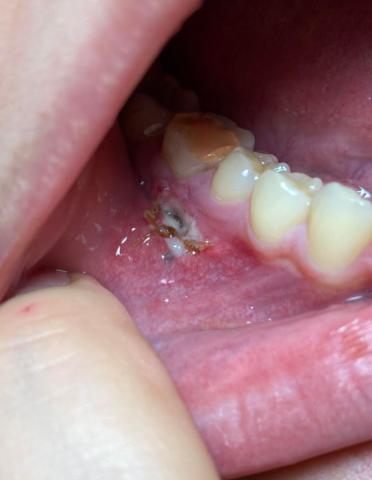

This clinical photo shows a localized infection in the posterior lower jaw, adjacent to natural teeth. An open gum lesion with visible debris and inflammation is present, suggesting an active infection at the soft-tissue and possibly underlying bone level.

Open ulcerated area on the gingiva

Visible yellow-brown debris consistent with infection

Surrounding gum tissue is red and inflamed

Adjacent teeth appear intact

Possible previous extraction or draining sinus tract